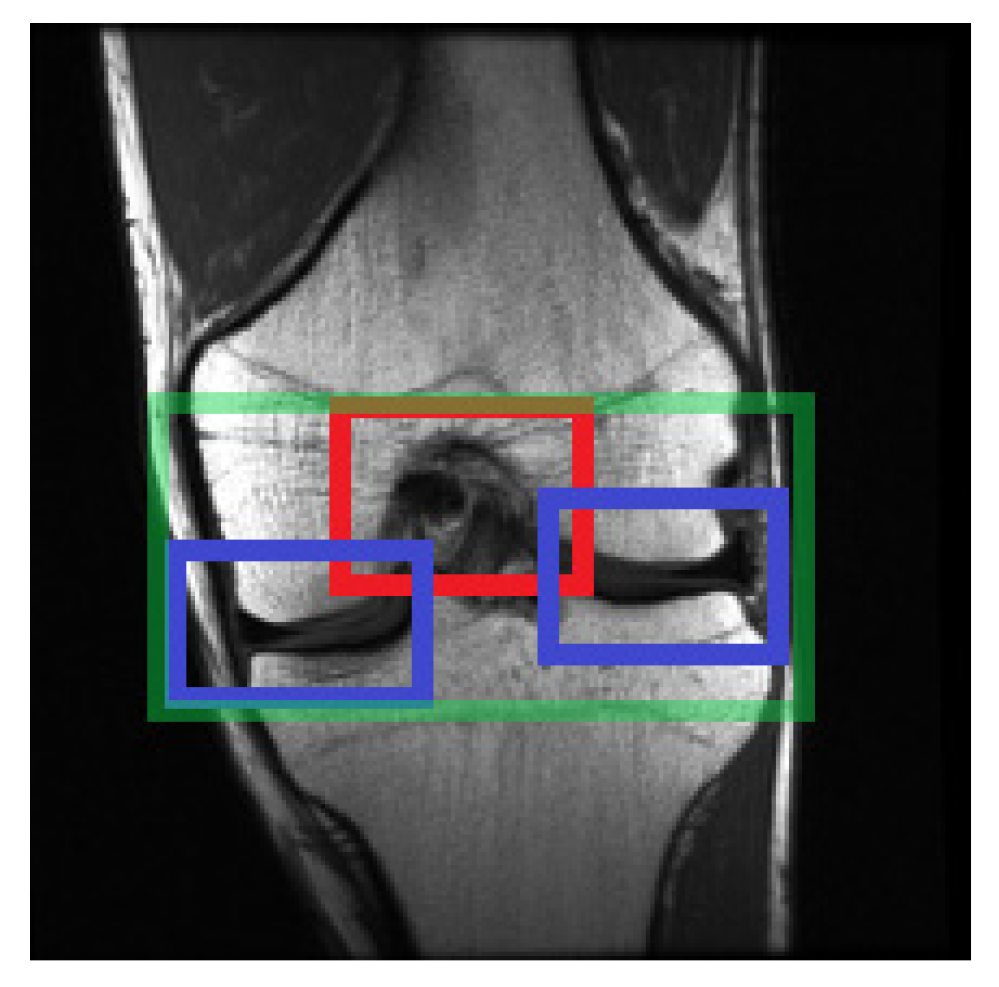

2.4. Selecting the Relevant Area

2.4.2. Selecting Relevant Regions on the Coronal Axis